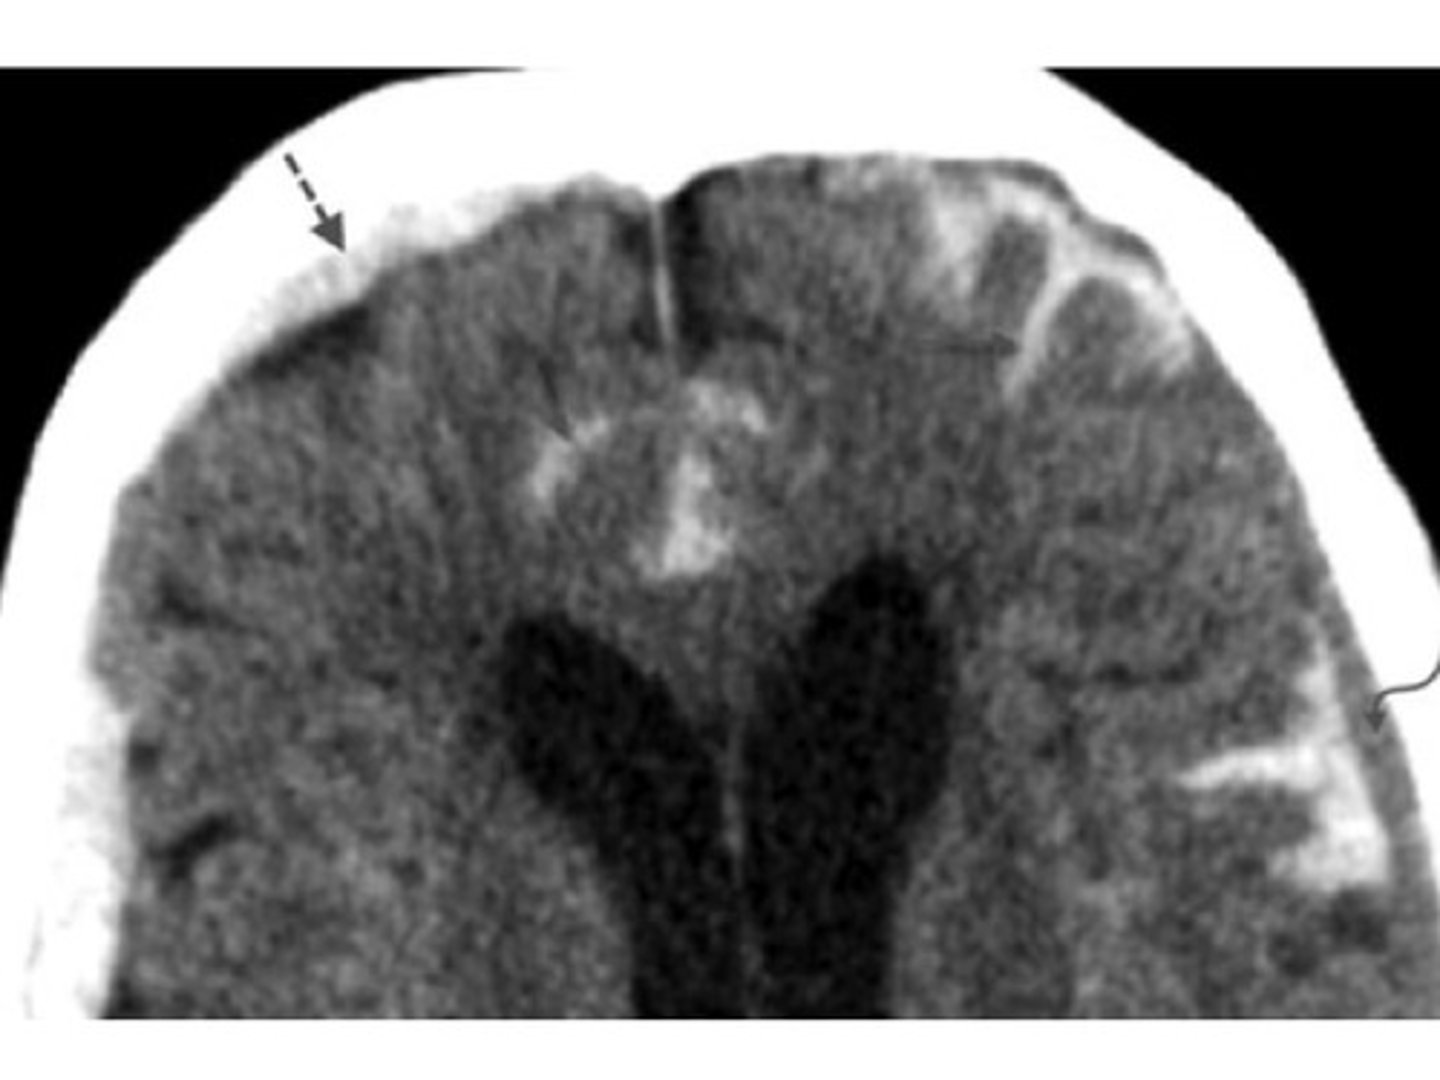

intracranial hemorrhage (ICH)

bleeding within the skull that leads to increased ICP and reduced cerebral perfusion

*traumatic or spontaneous

*major cause for neurologic morbidity and mortality

epidural hemorrhage

arterial bleeding between the skull and dura

*middle meningeal artery affected

subdural hemorrhage

venous bleeding between the dura and arachnoid

*due to rupture of bridging veins

intracerebral hemorrhage

bleeding within the brain tissue

ICH

presentation of what impairment/issues with what cranial structure?

- headache

- nausea/vomiting

- altered consciousness

- weakness

- speech or vision deficits

- seizures

- rapid neurological decline